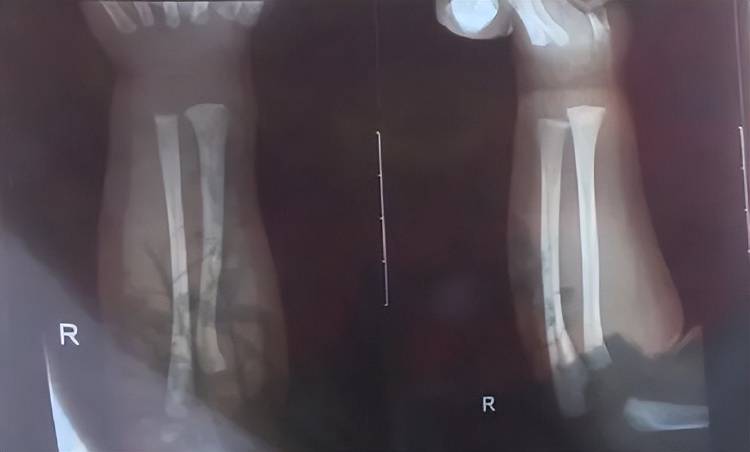

次日上午,孩子被带到附近医院检查,医生诊断发现他右手有两处骨折,第一处为右侧尺骨远端骨折,第二处为右侧桡骨远端骨折,随后医生给他做了石膏固定,“没想到,几天后孩子还被诊断出脑电图异常,医生建议复查cstk虚拟币。”

孩子被诊断发现两处骨折